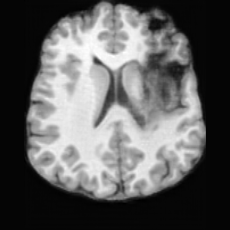

PathologicalSynthSR [18]Brain-ID [28]UNA [30]USBRefer to captionRefer to captionRefer to captionRefer to captionRefer to captionRefer to captionRefer to captionRefer to captionRefer to captionRefer to caption

Figure D.1: Comparison of pathology-to-healthy editing results on real stroke brain images from the ATLAS dataset [27].

Editing as Healthy Reconstruction for Patient Scans. Fig. D.1 illustrates the results of different methods applied to real stroke pathological brain images from the ATLAS dataset [27]. As shown, for relatively small lesions (first row), competing methods can partially reconstruct healthy brain structures, yet the results are noticeably inferior to those produced by USB. For larger lesions (second row), all other methods fail to recover the healthy regions, whereas USB successfully restores anatomically plausible healthy brain structures. These observations demonstrate USB’s superior ability to handle a wide range of lesion sizes and its robustness in generating anatomically plausible healthy reconstructions from real pathological scans, even though the model was trained solely on pseudo-synthetic pathological data.